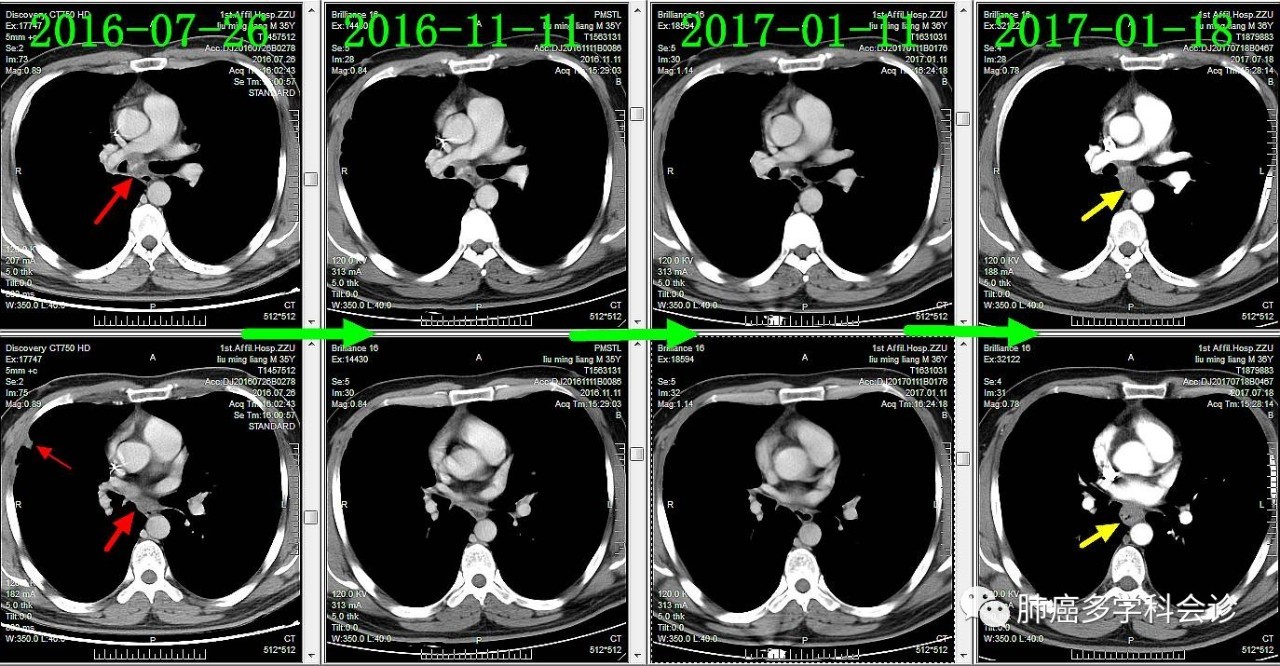

下面通过对比治疗过程中胸部CT变化,展示胸部肿瘤此消彼长的过程:

肺原发灶略有缩小

纵隔肿大淋巴结逐渐缩小

胸膜转移灶消失

食管转移灶从小到大

下面着重展示食管转移灶的发展过程。从2016-09-13(完成2个周期化疗)开始,上下两图分别为各时间点CT的上下两层: